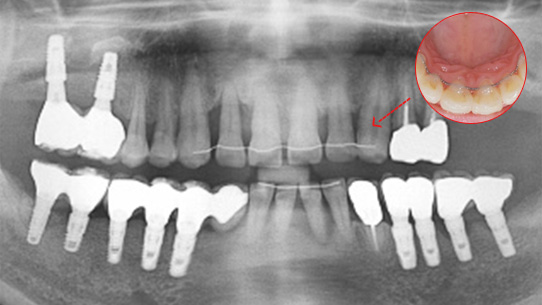

심한 염증과 기존 보철물의 오염상태가 심해 임플란트 17개를 진단받고 내원하신 환자분, 특히 앞니부분의 치조골이 많이 약해져 흔들림이 심하여 바로

치주치료를 시행하였습니다. 치주치료 2주 후 앞니 잇몸이 개선되어 발치 하지 않고 교정 유지장치를 이용하여 흔들림을 보완하였습니다.

오염된 보철물을 제거하고 임플란트 11개를 식립하였습니다.

심한 염증으로 치아가 흔들리는 상태

앞니 흔들림을 보완하는 유지장치 부착